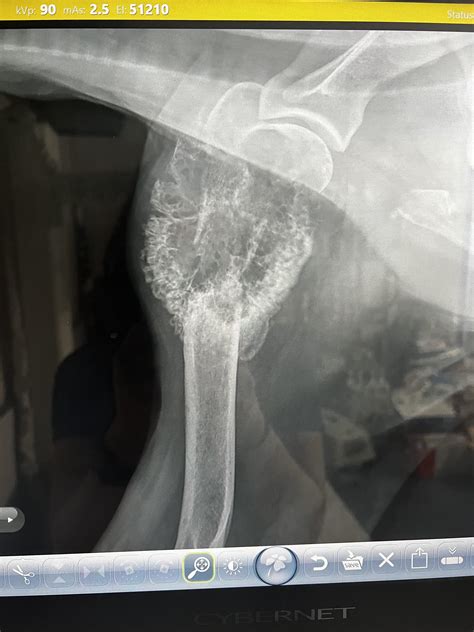

• Sunburst Pattern: Radiating spicules of bone formation that extend outward from the tumor into the soft tissue.

• Codman’s Triangle: A triangular formation of new bone that occurs when the tumor grows faster than the periosteum (the outer covering of the bone) can form new bone, resulting in an elevation of the periosteum.

• Soft Tissue Mass: Shadows outside the bone that suggest the tumor has breached the cortical bone and is invading the surrounding soft tissues.

Interpreting an Osteosarcoma X Ray requires a nuanced eye. Osteosarcoma is heterogeneous, meaning it can present in several different ways depending on its subtype and location. The appearance of the lesion often depends on whether it is predominantly osteoblastic (bone-forming) or osteolytic (bone-destroying).

• osteosarcoma x ray dog